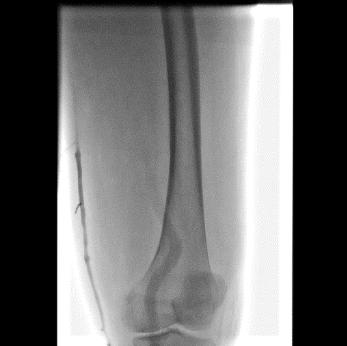

急诊造影:大腿段腘静脉通畅,股静脉通畅,见图3

图3